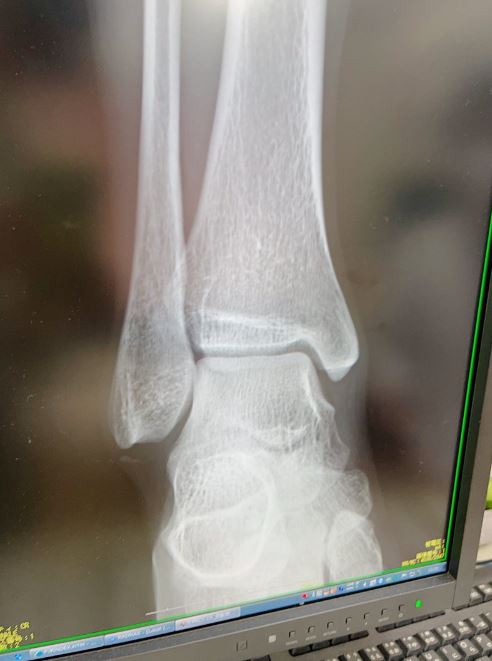

次いで、自身の足元の上にレントゲンの撮影機が構えられている様子の写真を掲載し「今日は朝から病院に行ってきましたー! レントゲンを撮るよ」と屈託無く続けています。

そして「骨に影響は無いみたい!やっぱり捻挫でした!」として「今日は安静にして病院後はずっとお家で作業してたよ」と、動画制作に取り組んでいた様子を伝えながらも「サポーター付けてもらったから 痛みも感じなくなってきた!」「ワンマンも控えているので無理しないようにしてます」と、9月11日開催のライブイベントに備えて回復に努める姿勢を見せています。